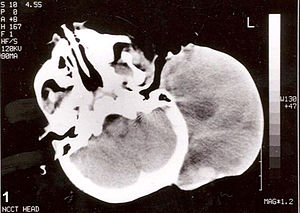

Diagnosis[edit | edit source]

- Rtg,

- CT,

- MRI,

- US,